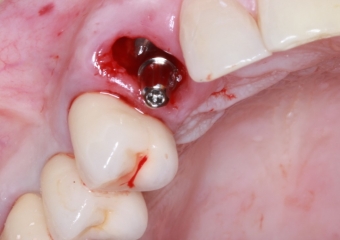

Foto implante instalado 03-10-16 - Clínica Cliniface

Foto implante instalado 03-10-16